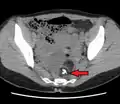

A complex cyst due to a dermoid as seen on CT. Arrow points to bone or teeth.